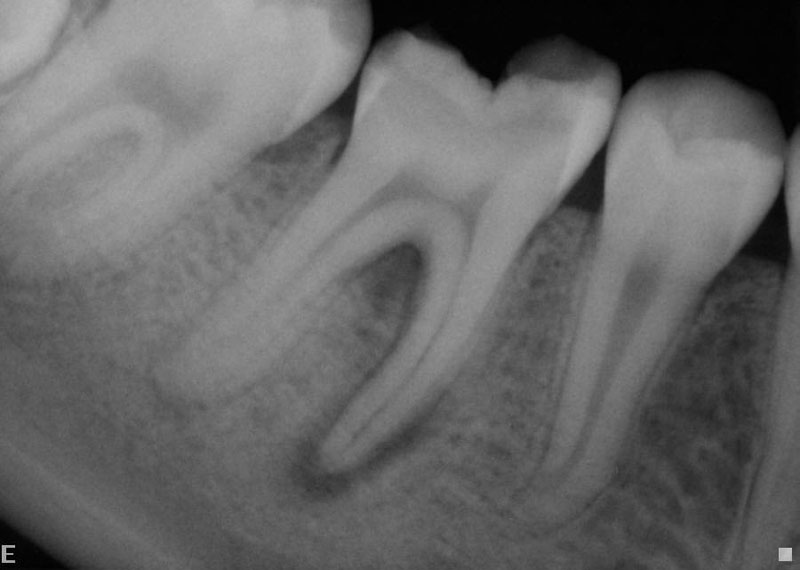

From www.creeksideendo.com

Root Canal Xrays Needed for Quality Treatment Creekside Endodontics How To Take Endo X Rays The term “periapical” refers to the fact. This is material from my root canal like an endodontist course. Getting working length radiographs during an endodontic procedure can be one of the most frustrating procedures on earth (well,. I wanted to share it bc often taking periapical radiographs during. Learn how radiographs are used for diagnosis, treatment, and postoperative evaluation in. How To Take Endo X Rays.